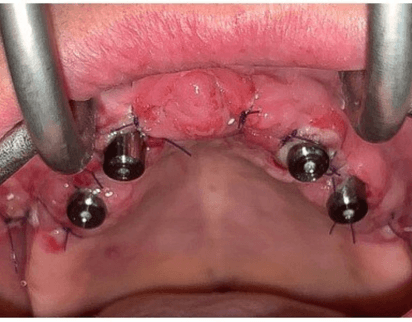

Colocamos los implantes cigomáticos según las guías quirúrgicas que hemos diseñado en planificación 3D.

Podemos hacer carga inmediata. Todo se realiza bajo sedación intravenosa monitorizada

Se colocan 4 implantes Zygoma según planificación 3D guiada bajo sedación IV, Carga inmediata a las 24 horas.

La paciente fue rehabilitada de forma definitiva a los tres de meses en su clínica origen.